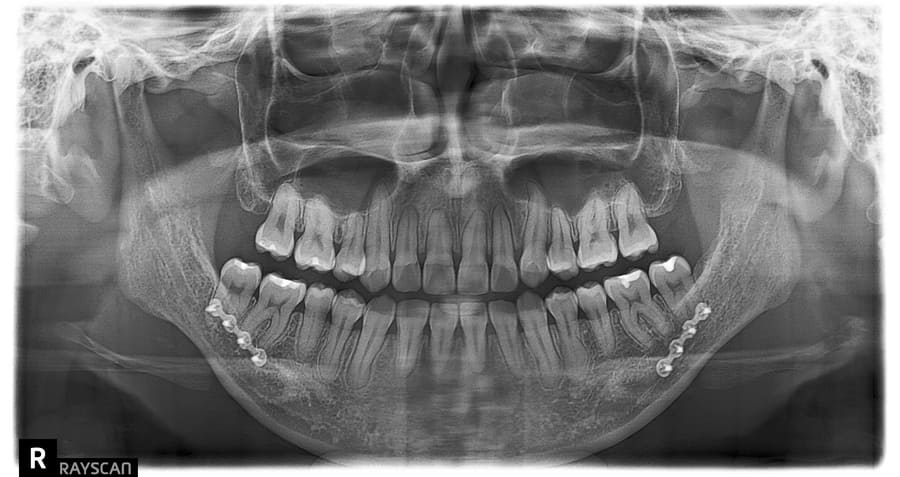

上下顎変形症に対する外科手術を併用した矯正治療《保険》

| 主訴 | 上下前歯の真ん中が合わない、かみ合わせを治したい |

|---|---|

| 診断名あるいは主な症状 | 上下顎変形症、交叉咬合 |

| 初診年齢 | 26歳 |

| 治療内容・装置 | マルチブラケット装置(上下表側からの矯正治療) 上下顎骨形成術(全身麻酔下の手術) |

| 抜歯・非抜歯 | 上下顎左右智歯抜歯 |

| 治療期間 | 1年7か月 |

| 費用 | 140,000円(保険適用、当院での自己負担額) |

| 治療のリスク | 歯の移動に伴う痛み 上下顎前歯部の歯根吸収 装置による口内炎 ブラッシング不良によるむし歯、歯周炎 外科手術後の痛み、腫れ、知覚鈍麻 |